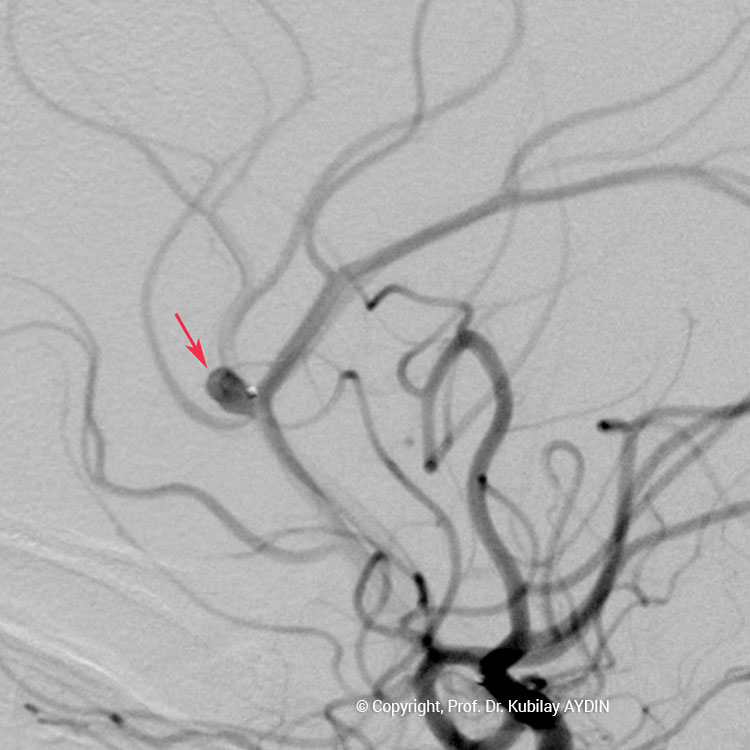

Tüm kapalı anevrizma tedavileri, hasta genel anestezi ile uyutularak gerçekleştirilir. Kapalı anevrizma tedavisinin tüm aşamaları, bacak atardamarı içine yerleştirilen 2 mm çaplı (kurşun kalemden daha ince) bir özel kateter yoluyla uygulanır. Bu küçük giriş noktasından damar içine çok ince (0.5mm çapında) ve yumuşak yapıda mikrokateter adını verdiğimiz özel plastik tüp gönderilir. Anevrizmayı kapatmak için kullandığımız bu mikrokateter, anjiografi cihazında izlenerek anevrizmanın bulunduğu damar içine yönlendirilir. İçi boş, çok ince ve yumuşak bir plastik tüp şeklinde olan mikrokateterin ucu, anevrizma kesesi içine yerleştirilir. Daha sonra bu mikrokateter içerisinden gönderilen platinden yapılmış çok yumuşak “koil” adı verilen tellerle anevrizma kesesi doldurulur. Koiller, anevrizma kesesi içinde bir yumak oluşturup, anevrizma içine kan girişini engeller. Anevrizma kesesi, koillerle tamamen doldurulup, anevrizma içine kan girişi tam olarak durduğu zaman, mikrokateter anevrizma içinden geri alınarak işlem tamamlanır. Anevrizmanın koil adı verilen özel tellerle doldurularak kapatılma işlemine, "koilleme" adı verilir. Anevrizmanın koillenerek kapatılması işlemi, oldukça güvenli ve etkili bir tedavi yöntemidir. Kanamamış beyin anevrizması olan hasta, koilleme yöntemi ile tedavi edildikten 1-2 gün sonra hasta normal günlük yaşamına dönebilir.